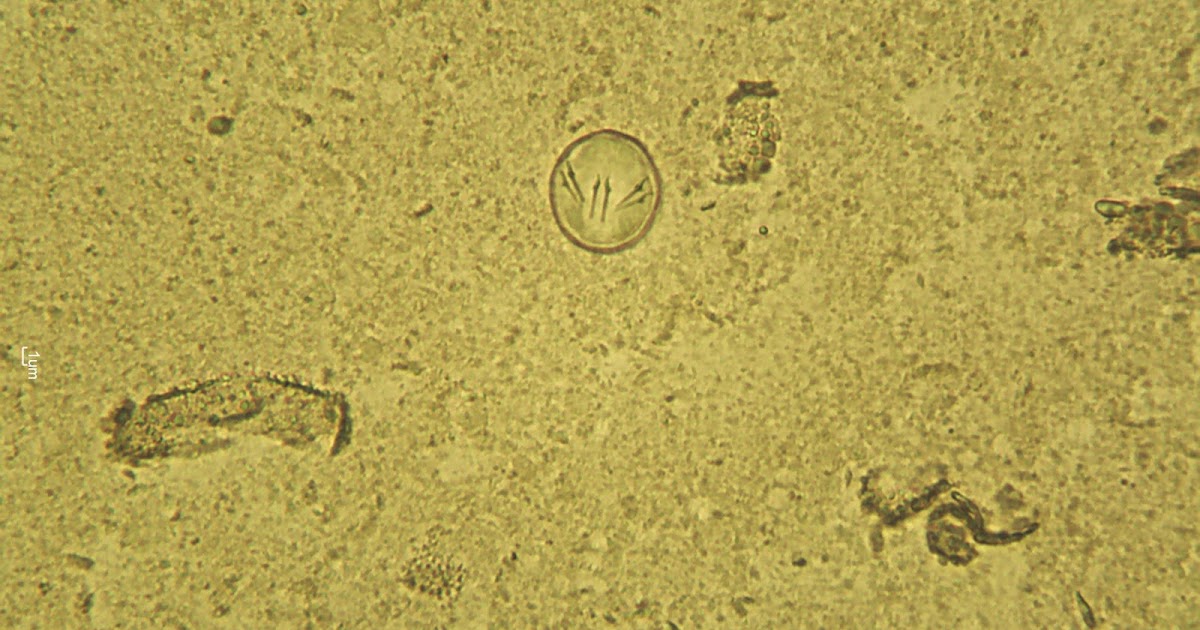

Common Endoparasites of Kittens National Kitten Coalition Grains Of Rice In Cat Poop Tapeworms are treatable with minima side effects and are. If you see small grains of rice around the tail or in your cat’s feces, call your veterinarian for an appointment. If you stumble upon worms in your cat’s poop that look like grains of rice, then you are most likely looking at tapeworms! Your vet can check a stool sample. Grains Of Rice In Cat Poop.